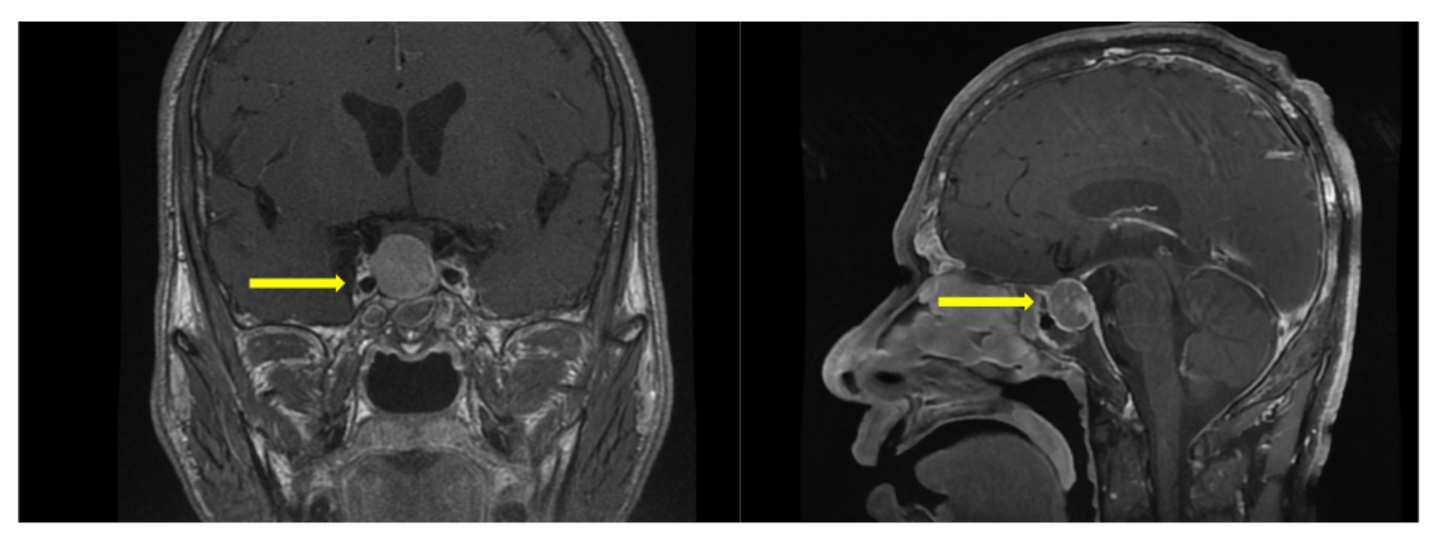

辅助检查:术前影像学提示鞍区占位;激素检查提示GH(>50 ng/ml)和IGF-1(431 ng/ml)升高。视力及视野检查提示左眼颞侧偏盲。

患者于2024年7月9日接受神经内镜经鼻鞍区占位切除术。术中依次完成黏膜瓣制作、双通道暴露、蝶窦前壁磨除、鞍底充分显露与切开硬膜,随后行肿瘤切除并实施鞍底重建。术后监测激素水平显示生长激素降至9.59 ng/mL,较术前显著下降。患者恢复平稳后出院。

术后随访复查提示生长激素持续下降,GH已降至3.89 ng/mL,呈良好生化反应趋势。术后半年复查影像学显示右侧海绵窦外侧可见残余病灶,但体积稳定,无明显进展。总体来看,患者激素水平控制理想。患者目前继续按照方案规律接受奥曲肽微球治疗,病情持续稳定。